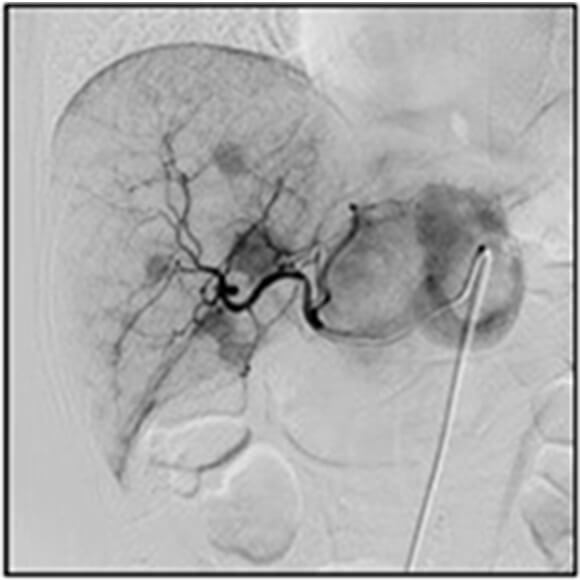

アンギオ検査部⾨

アンギオ検査とは⾜の付け根・⼿⾸・肘などからカテーテルと呼ばれる細い管を⾎管内に挿⼊し、造影剤を注⼊しながら⾎管のX線撮影を⾏う検査です。これにより⾎管の閉塞・狭窄やがんなどの臓器疾患の診断が可能となります。

近年、アンギオ検査は⾎管造影撮影による画像診断だけでなく、引き続き治療を⾏うIVR(InterVentional Radiology)が盛んに⾏われています。

治療部位に応じて⼿技はさまざまであり、⼼臓や四肢の狭くなったり詰まったりした⾎管にはバルーンと呼ばれる⾵船のついた管やステントと呼ばれる⾦属製の筒を挿⼊、または⾎管を拡張させるような薬を流すことで正常な状態に戻したり、症状を抑えるような治療を⾏います。がん疾患については、腫瘍を栄養している⾎管までカテーテルを進め、抗がん剤や塞栓物質を⽤い腫瘍を弱らせ、縮⼩させる動脈化学塞栓術を⾏います。その他、動脈瘤や外傷等による出⾎部位の⽌⾎については、コイルと呼ばれる塞栓物質により⾎管を詰まらせる⾎管塞栓術を⾏います。

当センターでは、⾎管内治療だけでなくX線透視下で⾏う検査及び治療についてはアンギオ装置を有効に活⽤できる体制を整備しております。

腹部⾎管

-

頭部⾎管

頭部⾎管